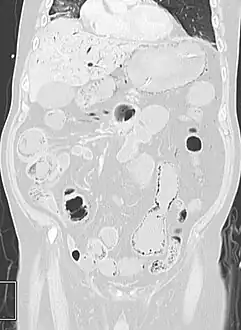

- Pneumatosis intestinalis in the coronal computed tomography in lung window. It can be seen next to gas entrapment in the bowel wall and gas in the stomach wall and in numerous vessels, including the portal vein into the liver.